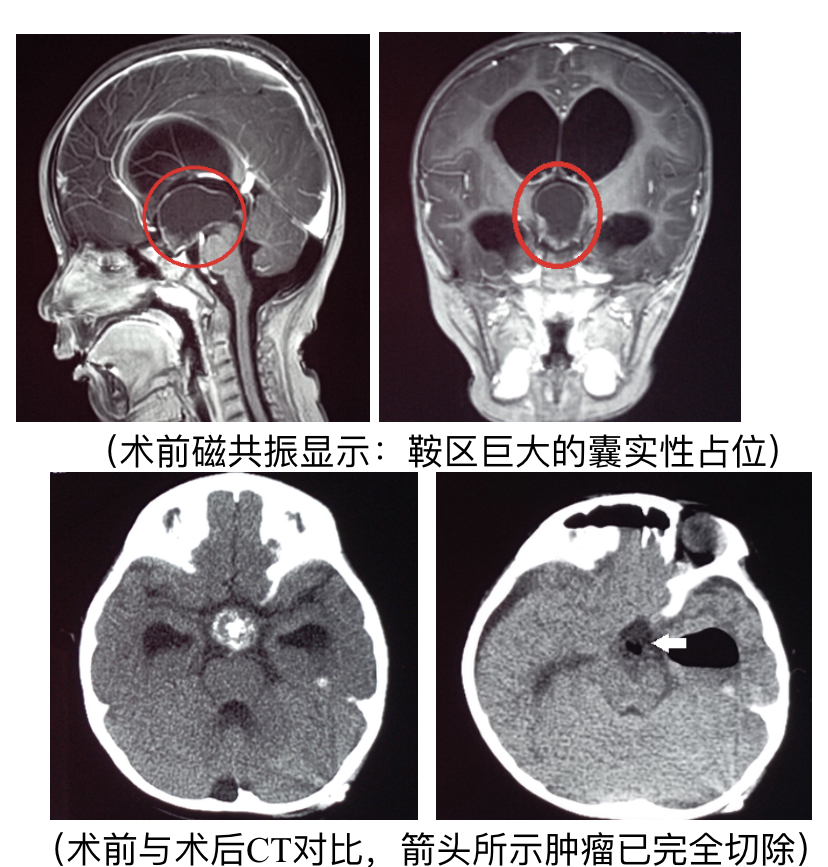

5cm,宽5cm的脑瘤,良性.目前没有任何不适,请问若手术,采用何种方式?

术前脑恶性肿瘤术后病理良性肿瘤 - 好大夫在线

手术全切肿瘤.术后恢复良好,未出现对侧肢体瘫痪和感觉障碍.